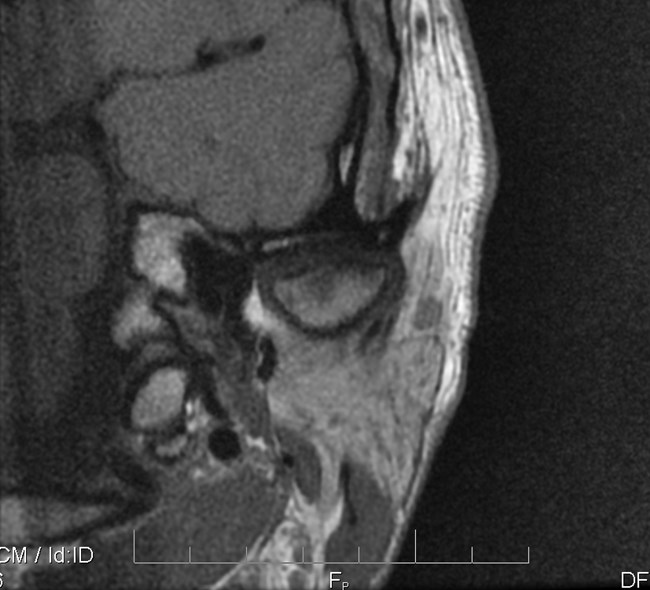

Na podstawie uzyskanych wyników badań zastosowano repozycyjną szynę zgryzową oraz terapię manualną narządu żucia. Po trzymiesięcznym leczeniu uzyskano poprawę modelu ruchomości żuchwy. W związku z utrzymywaniem się silnych dolegliwości bólowych zlecono dodatkowo badanie tomografii rezonansu magnetycznego (MR), w którym w zwarciu stwierdzono obustronne doprzednie przemieszczenie krążków stawowych (ryc. 5). W zwarciu na przekrojach czołowych widoczne było spłaszczenie powierzchni stawowej lewego ssż (ryc. 6). W rozwarciu pozycja obydwu głów żuchwy była doprzednia w stosunku do szczytów guzków stawowych, a nad głowami żuchwy leżały pasma przednie krążków stawowych. Przemieszczenie głowy żuchwy było bardziej nasilone w prawym stawie skroniowo-żuchwowym (ryc. 7).

Ryc. 6a i 6b. Przekroje czołowe MR ssż w zwarciu, obrazy PD-zależne. Widoczne spłaszczenie powierzchni stawowej lewego ssż.